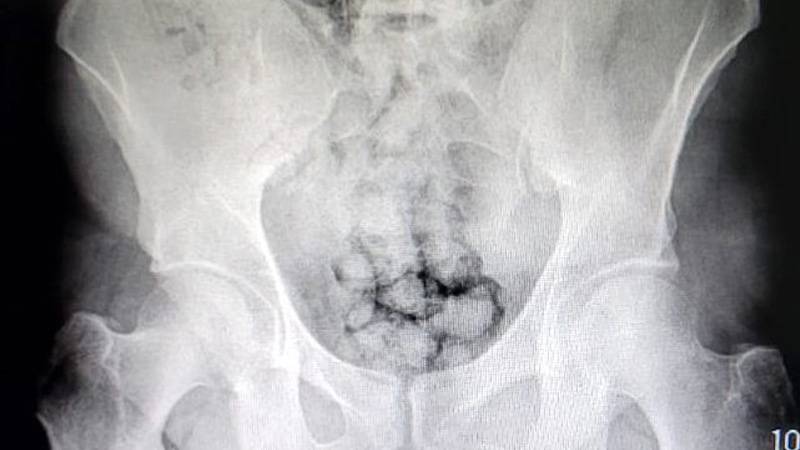

Röntgen çekildi, 60 kapsül uyuşturucu görüldü

Muayene edilmek üzere Kayseri Devlet Hastanesi'ne getirilen 2 şüphelinin röntgenleri çekildi. Röntgen çekimi sonrası şüphelilerin midesinde yaklaşık 60 kapsül içinde toplam 500 gram metamfetamin olduğu tespit edildi.